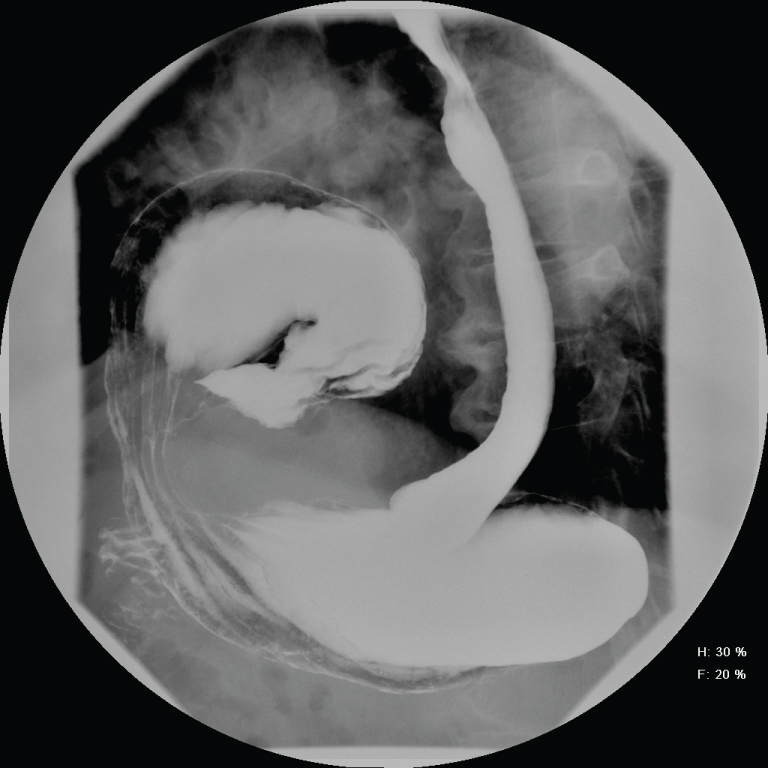

The Patient was admitted for a 23 hour observation. His oxygenation improved over night and was weaned to room air. He was discharged home after tolerating a diet. The following three weeks he complained of non-specific symptoms of vomiting/constipation, belching and not feeling well. He visited the emergency department and underwent a barium upper GI study that revealed mesoaxial gastric volvulus within a left diaphragmatic hernia and spontaneous gastric reflux (Figure 2).

Figure 2: Upper GI study with PO barium showing herniation of the antrum in the chest. View Figure 2